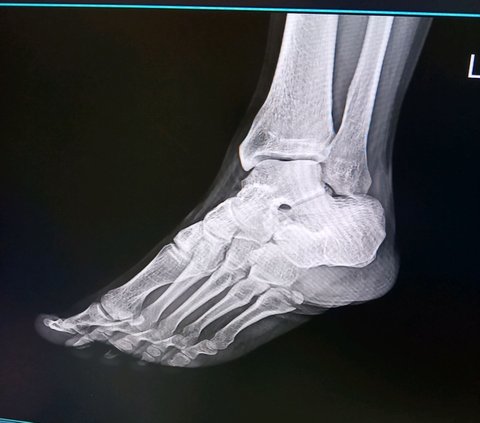

어이구, 엑스레이 보니까 골편도 크고요

이 부위가 인대가 붙어 있어서 계속 잡아당기는 부위예요.

잡아당기기 때문에 뼈가 안 붙습니다.

골절이 크긴 크네요.

골절이 커서 오래 걸리긴 할 거 같은데 그래도 붙긴 붙어요. 운동선수면 수술하라 하는데 선수 아니면 수술 안 해도 돼요. 여기는 잘 붙는 부위거든요.

이것도 위치마다 달라요. 세군데로 나눠서 1구역, 2구역, 3구역으로 나누는데, 3구역에서는 작은 자극에도 인쒈션이 강하게 나타나서 불안정하고, 1구역에서는 자극이 커야만 인쒈션이 나타나서 안정적이죠. 환자분은 1구역 골절이고요. 3구역은 골진 나올 때까지 깁스하고 걷지도 못하는데, 1구역은 깁스만 잘 하면 살살 걸어도 안 벌어져요. 그래서 3구역은 골진 늦게 나올 거 같다 싶으면 수술하라 하죠.

수술하면 전신마취나 하반신마취해야 하니 쉽게 생각할 일 아니고, 나중에 나사 빼는 수술도 또 해야 하는데 너무 힘들 거에요. 그리고 뼈가 상당히 갈라지는 형태로 부러져서 나사 하나로 안 되고 핀 여러 개를 세세하게 박아야 하니까 깁스만 하시는 게 낫지 않을까 싶네요.

전에도 말씀드렸던 것 같은데... 환자분이 다친 곳이 1구역이고, 1구역은 붙어 있는 힘줄이 넓게 포진되어 있어서요 잡아당기는 힘이 분산돼요. 그래서 깁스로 고정만 해주면 쉽게 안 벌어지죠.

깁스로 보호한 상태에서 조심해서 걷는 걸 전문용어로 프로텍티드 웨이트베어링이라 하고요. 1구역 골절은 이게 스탠다드에요. 위치도 1구역이고 피로골절 소견이 안 보여요.